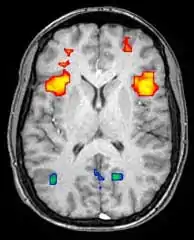

Functional magnetic resonance imaging

Functional magnetic resonance imaging (fMRI) and arterial spin labeling (ASL) relies on the paramagnetic properties of oxygenated and deoxygenated hemoglobin to see images of changing blood flow in the brain associated with neural activity. This allows images to be generated that reflect which brain structures are activated (and how) during the performance of different tasks or at resting state. According to the oxygenation hypothesis, changes in oxygen usage in regional cerebral blood flow during cognitive or behavioral activity can be associated with the regional neurons as being directly related to the cognitive or behavioral tasks being attended.

Most fMRI scanners allow subjects to be presented with different visual images, sounds and touch stimuli, and to make different actions such as pressing a button or moving a joystick. Consequently, fMRI can be used to reveal brain structures and processes associated with perception, thought and action. The resolution of fMRI is about 2-3 millimeters at present, limited by the spatial spread of the hemodynamic response to neural activity. It has largely superseded PET for the study of brain activation patterns. PET, however, retains the significant advantage of being able to identify specific brain receptors (or transporters) associated with particular neurotransmitters through its ability to image radiolabeled receptor "ligands" (receptor ligands are any chemicals that stick to receptors). There is also significant concern regarding the validity of some of the statistics used in fMRI analyses; hence, the validity of conclusions drawn from many fMRI studies.[22]

With between 72% and 90% accuracy where chance would achieve 0.8%,[23] fMRI techniques can decide which of a set of known images the subject is viewing.[24]

Recent studies on machine learning in psychiatry have used fMRI to build machine learning models that can discriminate between individuals with or without suicidal behaviour. Imaging studies in conjunction with machine learning algorithms may help identify new markers in neuroimaging that could allow stratification based on patients' suicide risk and help develop the best therapies and treatments for individual patients.[25]